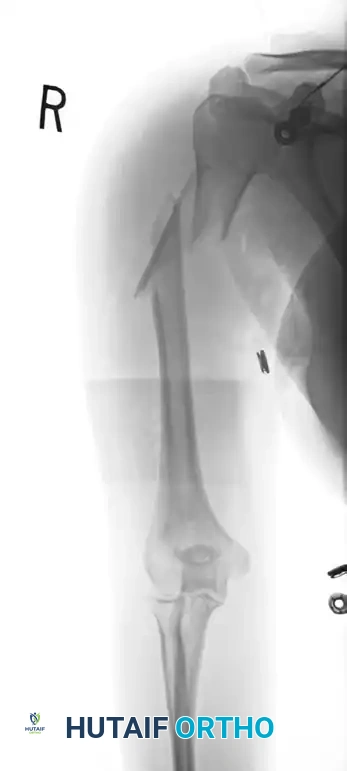

Figure 57-38 A: Segmental shaft fracture with extension into the proximal humerus.

Figure 57-38 B: Long plate utilized to obtain secure fixation across the segmental defect.

Figure 57-38 C: Lateral radiographic view demonstrating secure fixation with a long plate.